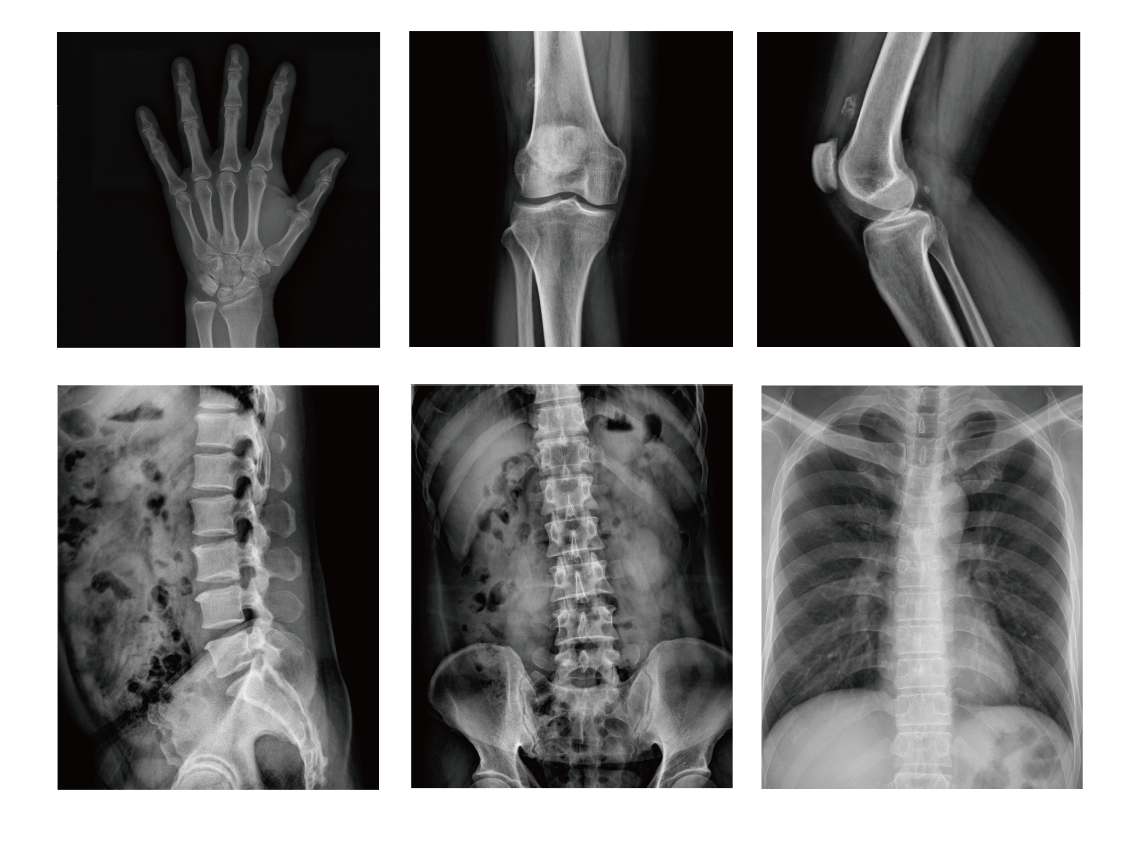

移动式X射线机不仅一机多用,在隔离病房、ICU、急诊室、呼吸科及疾控中心的危、急、重症患者的检查诊断中发挥了非常重要的作用,为重症患者的诊断与治疗赢得了时间,同时也为不能活动的及不适宜活动的隔离患者提供可移动的诊断方案,减少医患接触传染,保护医务人员的安全。

DR改善了床旁胸片的条件和图像质量,床旁胸部摄影在老年人、新生儿外伤性患者、尤其是急危重患者的抢救、治疗过程中起着相当重要的作用。因为新生儿体格纤小、娇嫩、胸部薄而脂肪软组织厚,肺含气量小的生理特点,所用kv及mAs要低于成人。

对于危重、吸氧、心电监护的病人用传统X光机拍片条件难掌握,黑白对比清晰度往往很难达到理想诊断要求,易造成误诊漏诊,康达医疗移动DR采用新的高频逆变技术与数字化拍片系统,不仅可以解决上述难题,而且成像清晰稳定。低剂量曝光成像技术,剂量敏感,信噪比高,成像需求剂量小,将散射线降低,大幅度减少受检人员及操作人员所受的辐射伤害。